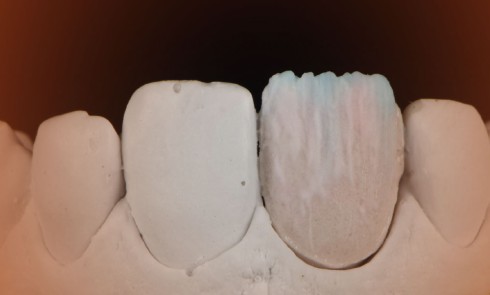

Article réservé à nos abonnés Le protocole e_LAB : les étapes clés

Le relevé de la couleur en dentisterie esthétique peut être considéré comme un challenge que ce soit pour le dentiste...